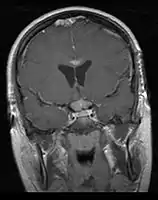

CNS Germinoma

- Mainly located in midline structures, suprasellar region or pineal gland, also basal ganglia and hypothalamus

- Whole ventricular volume: 3rd, 4th, lateral, prepontine cistern